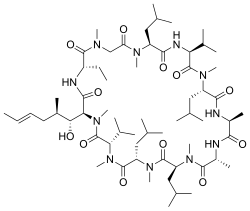

Das Phänomen der Transzytose ist jedoch nicht auf Makromoleküle beschränkt. Wenngleich der genaue Mechanismus nicht immer geklärt ist, so konnte gezeigt werden, dass auch kleine Peptide und niedermolekulare Substanzen auf diese Weise in die Zelle gelangen und diese passieren können. Eine Vektorisierung zum Zweck der Passage der Blut-Hirn-Schranke ist somit auch mit kurzen Peptidsequenzen möglich. Als Vektoren für Wirkstoffe, wie beispielsweise Doxorubicin, fanden unter anderem basische Protegrin-Abkömmlinge, wie beispielsweise Syn-B,[53][54] und das aus der Homöodomäne von Antennapedia, einem Transkriptionsfaktor von Drosophila, abgeleitete Penetratin[55] Anwendung. Ein anderer Peptid-Vektor ist das aus elf überwiegend basischen Aminosäuren bestehende und aus der Transduktionsdomäne des HI-Virus isolierte HIV-TAT (engl. Trans-Activator of Transcription).[51][56] Ein Peptid mit ähnlichen Eigenschaften ist das aus 27 Aminosäuren aufgebaute Transportan, ein zellpenetrierendes Peptid.[57]